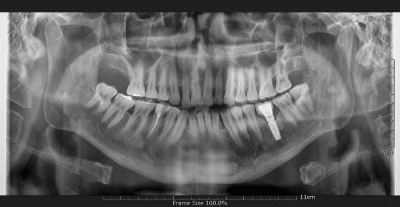

환자분(김ㅇ진님)은 #34 부위에 임플란트 수술을 받으셨습니다. 수술은 약 30분 만에 순조롭게 마쳤습니다.